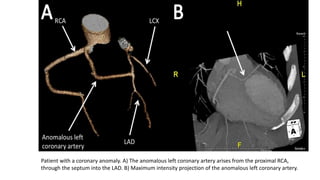

Patient with a coronary anomaly. A) The anomalous left coronary artery arises from the proximal RCA,

through the septum into the LAD. B) Maximum intensity projection of the anomalous left coronary artery.

Patient with acoronary anomaly. A) The anomalous left coronary artery arises from the proximal RCA, through the septum into the LAD. B) Maximum intensity projection of the anomalous left coronary artery.